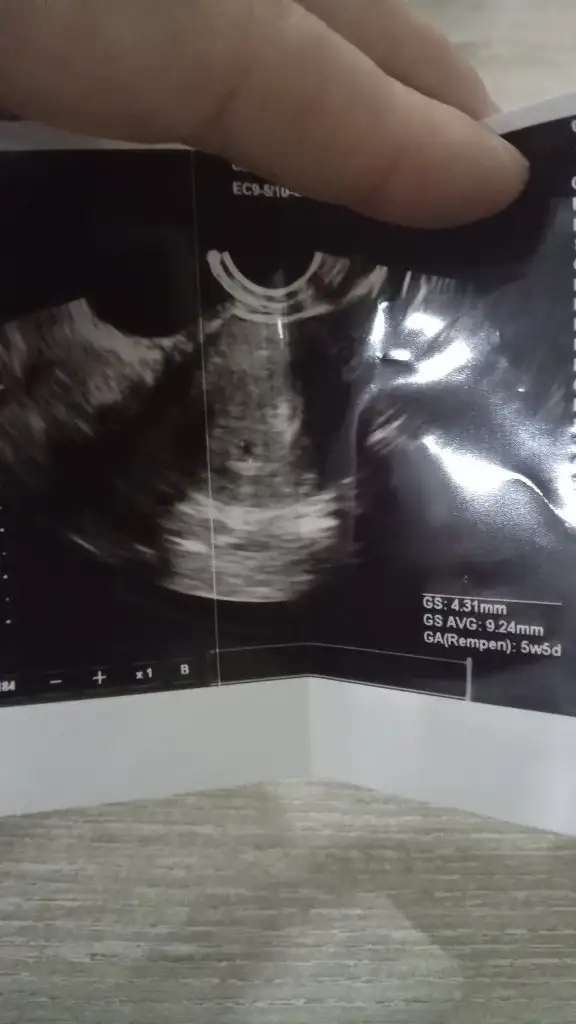

Bana da yorum yapar mısınız vajinal usg 6+6

• 03B2C2FF-740C-448A-BAF2-933D726BF0E7.webp

03B2C2FF-740C-448A-BAF2-933D726BF0E7.webp

31,7 KB · Görüntüleme: 101